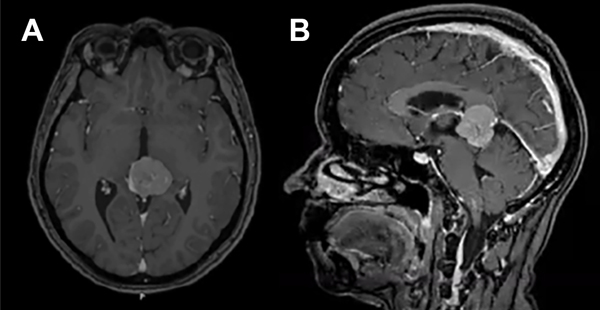

En ambos casos, pero con distinta premura, indicaremos la realización de una tomografía de encéfalo con y sin contraste y una resonancia magnética de encéfalo y columna con gadolinio (Fig.1), y angiorresonancia de vasos intracerebrales que incluya tiempo venoso para caracterizar lo más fidedignamente el tamaño, extensión y compromiso de estructuras elocuentes, presencia de calcio, componente sólido y quístico, y las características vasculares que representan el entorno del tumor o la lesión per sé, que condicionarán la estrategia de la resección quirúrgica. A pesar de los avances en el diagnóstico por imágenes debemos tener presente que ellas no nos aportan demasiado en lo que respecta a la estirpe tumoral, quizás una presunción de la misma.

Figura 1. A. Corte axial y B. Corte sagital de resonancia magnética con Gadolíneo que toma contraste, en región pineal.